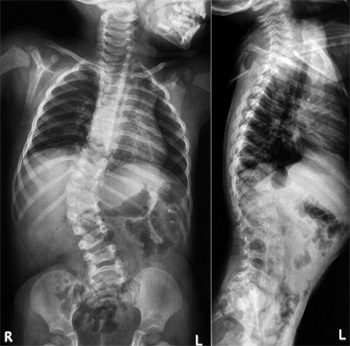

Рентгенография позвоночника является основным методом диагностики сколиоза. При подозрении на сколиотическое искривление рентгенографию необходимо проводить не реже 1-2 раз в год. Первичная рентгенограмма проводится в положении стоя, а в последующем рентгеновские снимки выполняются в положении лежа с умеренным растягиванием в двух проекциях, что позволяет оценить истинную деформацию. Для диагностики сколиоза, определения его степени, признаков стабилизации и прогрессирования выполняют две рентгенограммы позвоночника в задней проекции: одну - в горизонтальном положении пациента лежа на спине, вторую - в вертикальном положении. Фокусное расстояние должно быть одинаковым (120 - 150 см). При наличии реберного горба под спину с вогнутой стороны грудной клетки подкладывают валик толщиной равной высоте горба. В случае выраженной кифотической деформации выполняют рентгенограмму в боковой проекции в положении пациента лежа таким образом, чтобы к кассете прилежала выпуклая сторона позвоночника

Для диагностики сколиоза, определения его степени, признаков стабилизации и прогрессирования выполняют две рентгенограммы позвоночника в задней проекции: одну - в горизонтальном положении пациента лежа на спине, вторую - в вертикальном положении. Фокусное расстояние должно быть одинаковым (120 - 150 см). При наличии реберного горба под спину с вогнутой стороны грудной клетки подкладывают валик толщиной равной высоте горба. В случае выраженной кифотической деформации выполняют рентгенограмму в боковой проекции в положении пациента лежа таким образом, чтобы к кассете прилежала выпуклая сторона позвоночника.